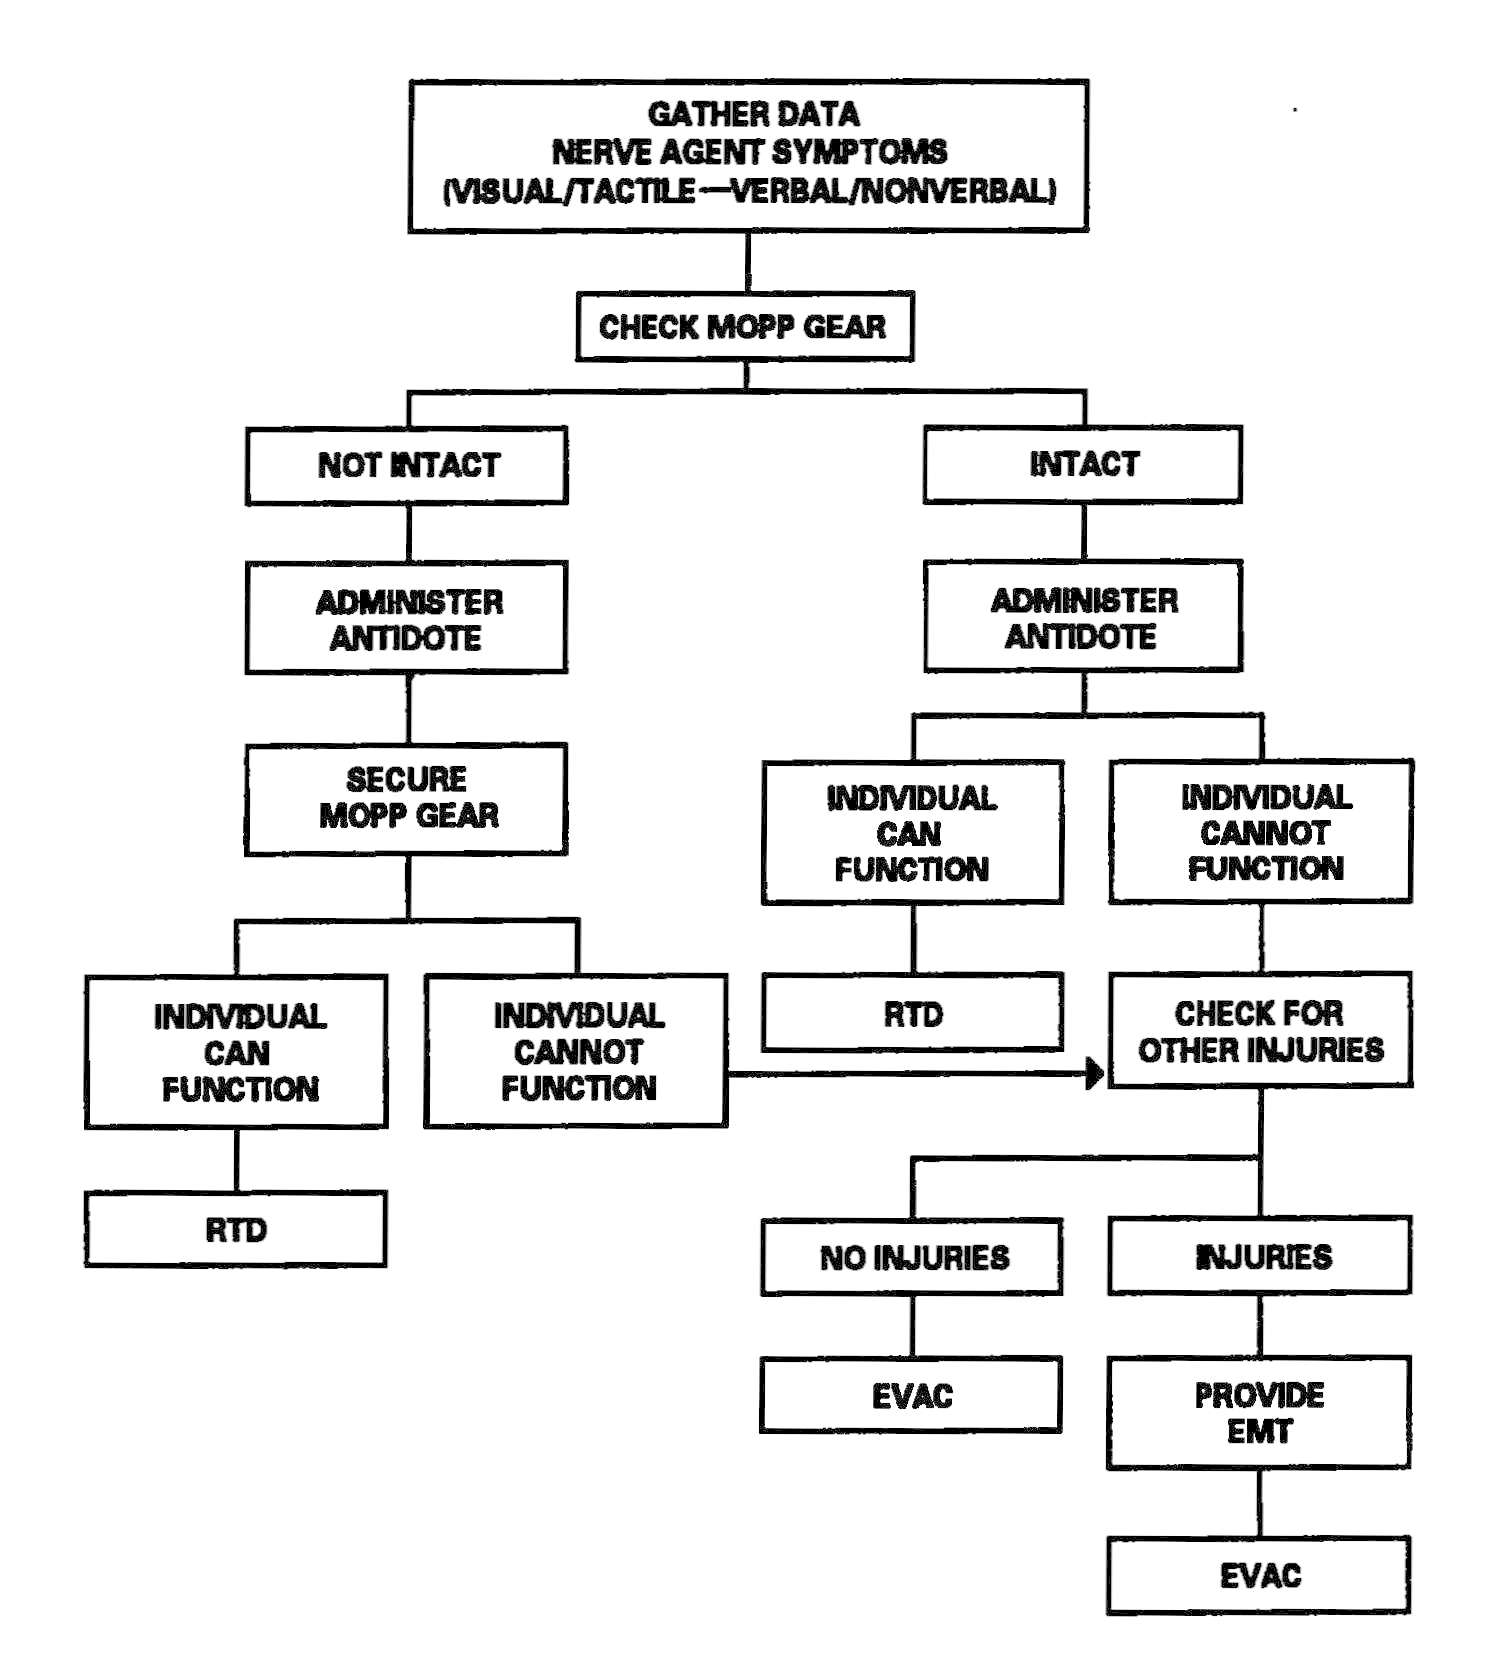

The HSS personnel make an appraisal of the supported mission to determine the expected patient load. Once the appraisal has been accomplished, HSS personnel prepare for the HSS mission by assigning personnel responsibilities. Using triage and EMT decision matrices for managing patients in a contaminated environment improves treatment proficiency. See Figure 2-1 for a sample decision matrix. Training HSS personnel in the use of simple decision matrices should enhance their effectiveness and contribute to a more efficient battlefield HSS process. Prior training for designated nonmedical personnel in patient decontamination procedures will enhance their effectiveness in the overall patient care mission. See Appendix D for planning factors on the estimation of NBC casualties.

Figure 2-1. Sample triage and emergency medical treatment decision matrix.